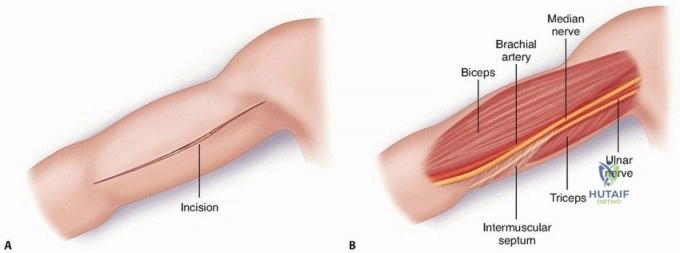

The Anterolateral Approach

The skin incision is made along a line connecting the coracoid process to the lateral epicondyle of the humerus. The length of the incision is dictated by the fracture pattern and the templated plate length. Subcutaneous tissues are dissected, taking care to identify and protect the cephalic vein, which can be retracted either medially or laterally depending on the exact proximal extent of the exposure.

The deep fascia is incised in line with the skin incision. The biceps brachii muscle is identified and mobilized medially, exposing the underlying brachialis muscle. At this juncture, the surgeon must decide on the specific handling of the brachialis muscle based on the fracture location.

For midshaft fractures, the brachialis muscle is split longitudinally down its midline. Because the medial half is innervated by the musculocutaneous nerve and the lateral half by the radial nerve, this longitudinal split is an internervous plane that preserves the function of both segments. The split is carried down to the periosteum, and the muscle halves are elevated off the anterior humerus. The lateral half of the brachialis acts as a protective muscular cushion between the retractor (and subsequently the plate) and the radial nerve.